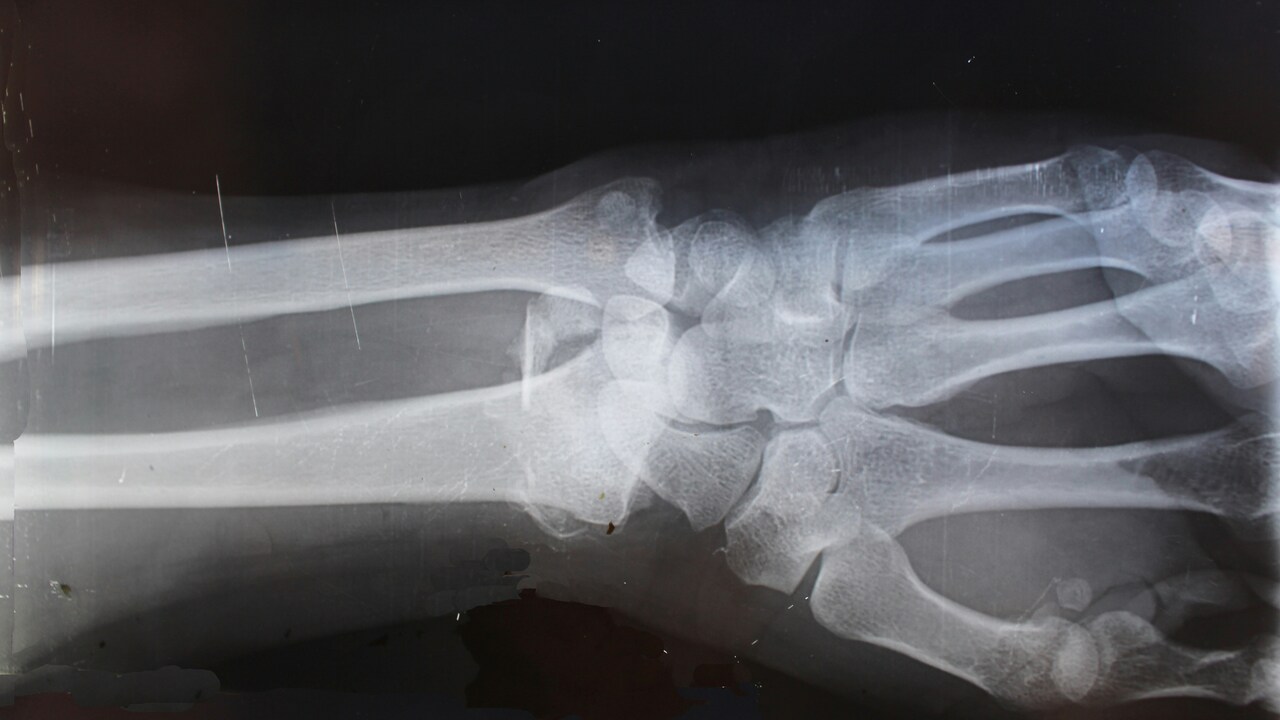

Traumatologist Vitaly Skakun from the center “healthy” center, said that the most common trauma in people who skate in scooters is a fracture of the radius connecting the elbow to the brush. According to him, when a person falls, he instinctively puts his hands forward to soften the impact, but this usually leads to the breaking of the wrist or forearm. Sometimes such injuries are serious and require surgery.